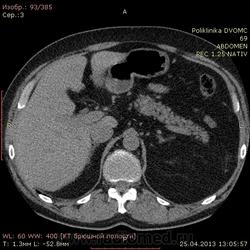

Уважаемые коллеги КТ-шники 2 часа ищу холедох, все перерыл, пересравнивал. Четко его так и не нашел, а в книжках пишут(можт обманывают?), что должен быть виден всегда. В сязи с этим огромная просьба: помогите!!!! и ткните, наконец, стрелкой в то место куда надо смотреть...спасибо.

Ткнуть, говорите? Это можно. Вспоминаем анатомию: гепатиколедох расположен в печеночно-двенадцатиперстной сваязке кпереди от воротной вены.